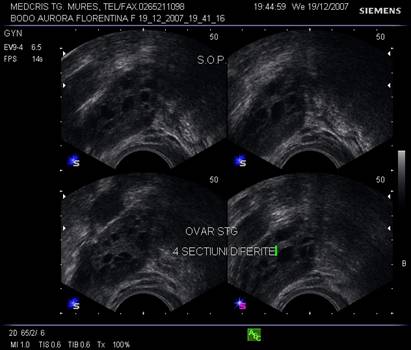

Fig. nr.374. Ovar in cadrul unui sindrom de ovar polichistic , cu multiplii foliculi (peste 7- 10 pentru fiecare sectiune ) dispersati in intreaga masa ovariana, de talie mica sub 5- 6 mm diametrul folicular

Fig. nr.375. Sindrom de ovar polichistic sub tratament cu methformin, se remarca la nivelul ovarului stang multiplii foliculi de talie mica dispusi periferic.